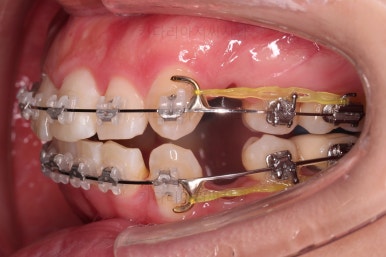

처음 장치를 부착한 사진입니다.

이번에 동래교정치과 선택한 장치는 엠파워 클리어라고 하는 자가결찰 세라믹 장치인데요.

흔히들 클리피씨라고 알고 계신 장치의 종류입니다.

엠파워와 클리피는 제조국만 미국, 일본으로 차이가 나고 큰 틀에서는 같은 장치라고 보시면 됩니다.

동래교정치과 장치 부착 사진인데요.

세라믹이라 비교적 장치가 많이 눈에 띄지 않고요.

입은 장치의 볼륨감으로 약간 튀어나오는 모습입니다.